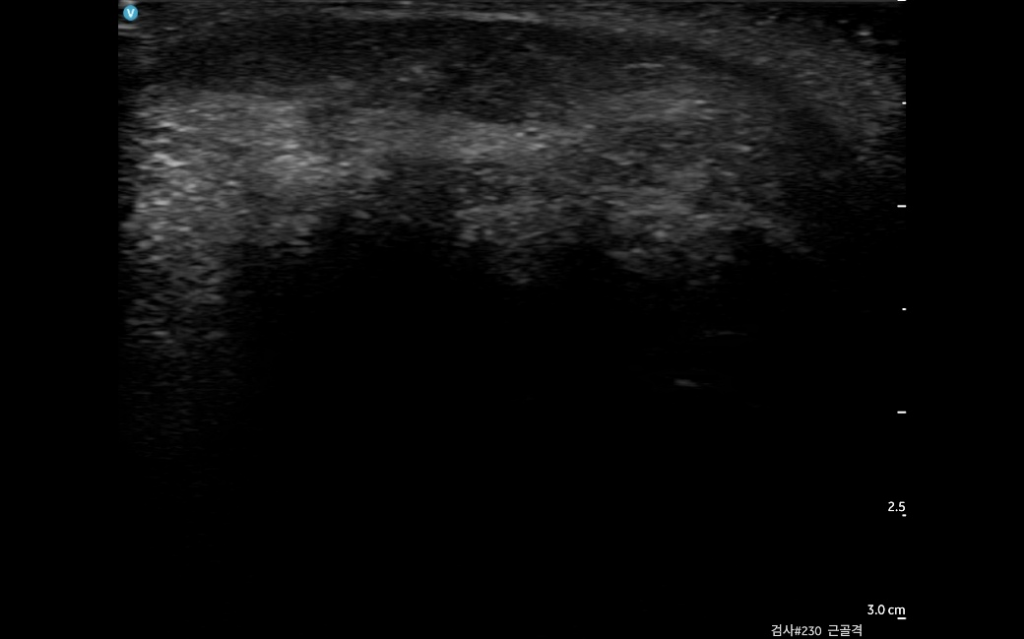

눈밑지방재배치했는데 한쪽만 불룩하게 멍울이 생겼어여 ㅜ 붓기라고 기다리라했는데 도저히 사람몰골이 아니라 초음파를 봤거든여

여기병원 원장님은 지방이나 필러론 안보이고

염증덩어리로 보인다는데 다른 원장님들 의견이 궁금합니다 ㅜ

• 1번 째 사진

첨부하신 초음파사진만으로는 알기가어렵습니다 해당병원 원장님과 상의하시는게 맞습니다.